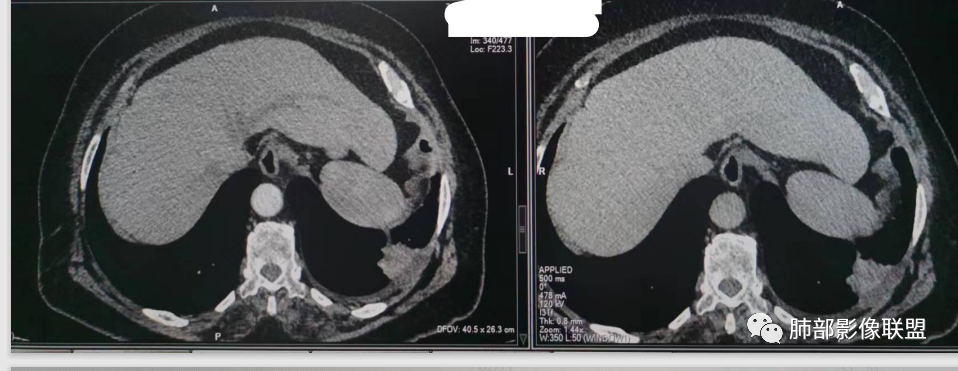

而且旁边这么宽的少,所以觉得很奇怪,不太符合,我是怀疑与照片有关。

你对比一下两侧的密度。肌肉密度不一样。

胸壁的组织,除非你怀疑胸壁转移结节。

转移淋巴结。

局部侵犯。有差异。

我只是邓较瘦:这个是侵犯出去不是淋巴结吧?

南边:不是,你看看强化与淋巴结不一致。

我只是邓较瘦:强化与肿瘤差不多。

南边:是。